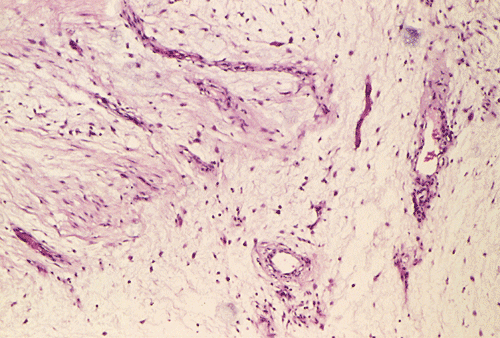

Panel A, B, and C are taken from the one area. Panel D, E, F, and G are taken from another area. Panel H and I are taken from areas with similar histologic features but distinctly separately on the same slide.

On low-magnifaction (Panel A and D), the lesional tissue appears to have generalized myomatous changes. No entrapped skeletal muscle fibers are found. The tumor cells tended to group into areas with variable cellularity that range from low- to, at most, moderate-cellularity. The hypocellular areas (Panel  B and C) contain sparsely spaced bland spindle cells in a bluish myxomatous background. The nuclei are elongated and mostly normochromatic. A few hyperchromatic nuclei are present and they are compatible with degenerative atypia (ancient change).

Islands with increased cellularity are present in some areas (Panel D, E, F, and G). These islands comprise about 30-40% of the lesional tissue. The cytologic features of the tumor cells in these areas are almost identical to that of the hypocellular areas except that the cellularity was increased. No mitotic figures are found in these areas. Focal hypervascularity are often found in areas with hypercellularity. No cellular condensation around blood vessels are noted (Panel  H and I).